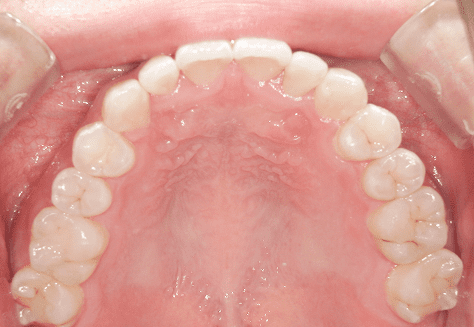

M.M

治療前

治療後

主訴

嚙み合わせが悪い。八重歯が気になる。

診断

叢生・反対咬合

年齢/性別

10代/女性

抜歯部位

非抜歯

使用装置

インビザラインファースト→インビザラインフェーズⅡ(部分的にワイヤーにて処置)

保定装置

上下ビベラリテーナー

診察料金

ファースト時:0円×16回

フェーズⅡ時:5,500円×9回

ワイヤー併用時:8,800円×2回 -

治療期間

2年7カ月